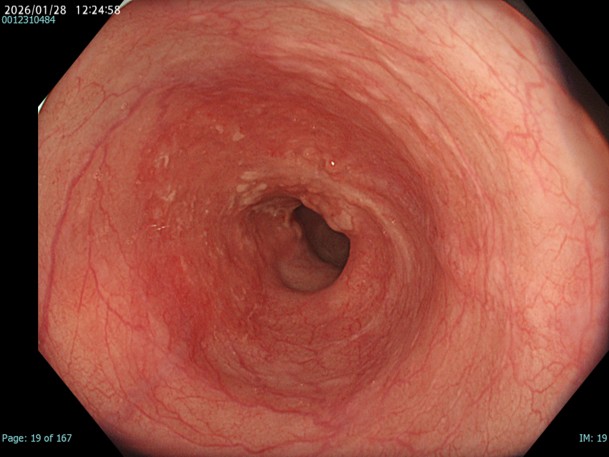

• 白色光観察(中遠景)

強調設定:A3

図1

胸部中部食道でやや粗造で血管透見が落ちているが、明かなDLは指摘が困難であり、色調も周囲粘膜とほぼ同等の為、この画像のみで腫瘍性変化を診断することは困難である。